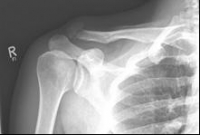

Pictures: Here, an angle-stable plate was used to supply the clavicle fracture near the shoulder joint. This plate makes it possible to anchor many screws in the fragment and thus obtain a good stabilization.